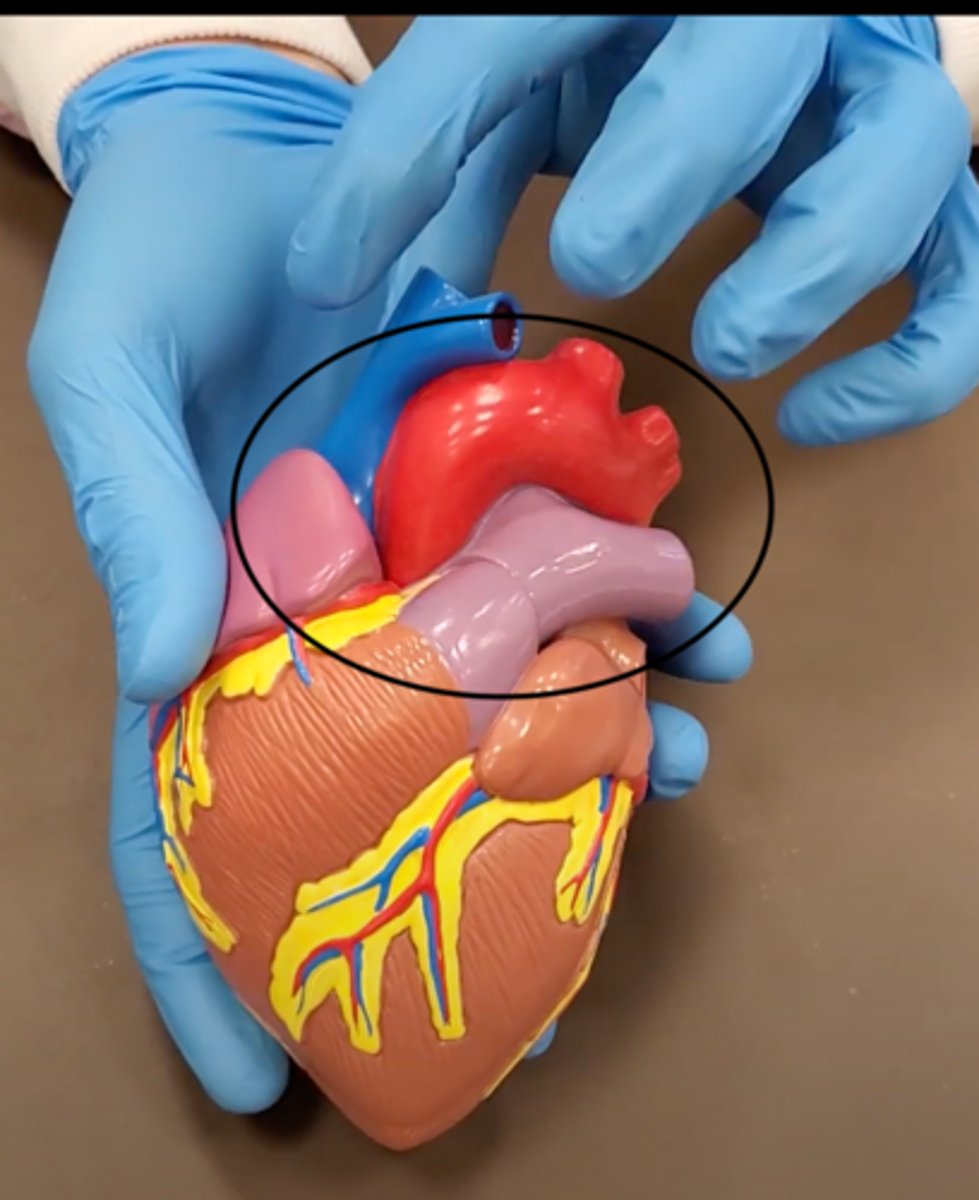

pulmonary trunk (model)

yellow sash of fat that tells you this if the front side of the heart (model)

t-shaped ribbon of fat on back side of heart (model)

Left ventricle (model)

has the most muscle mass because it has to pump blood to the whole body

apex (model)

base (model)

where everything connects